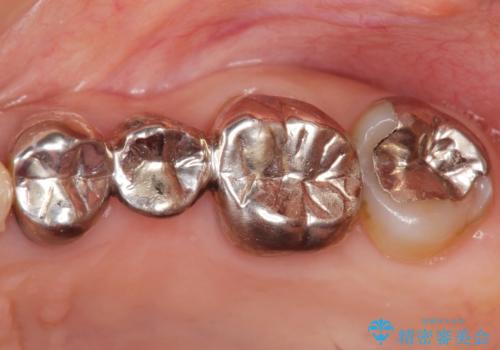

- 「老朽化し古くなった銀歯を白いものにやりかえたい。」と希望され来院されました。

銀歯の下には再発した虫歯やセメントの漏出が見られ、丁寧に除去したのちセラミックによるクラウン・ブリッジ補綴を行います。

適合や精度の悪い銀歯は、時間の経過とともに虫歯の再発リスクが高まります。